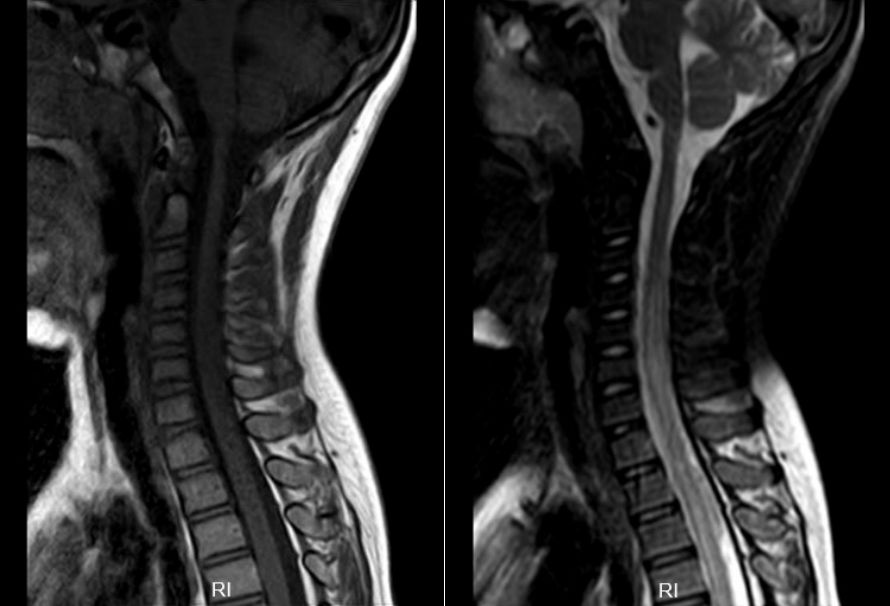

综合以上检查,诊断考虑“病毒性脑脊髓炎”。予“阿昔洛韦”抗病毒、“金璐捷”营养神经、“甲强龙”激素冲击等对症治疗15天,好转后出院。出院后继续口服“强的松”治疗1年余。出院后平时可下地行走,但未能坚持长时间,爬楼梯吃力,可短程小跑,剧烈运动或行走时间长后有腰背部疼痛、四肢酸痛,休息后可好转,感冒后症状加重,行走困难,站立不稳,伴腰背疼痛及排尿困难,有时大便失禁。感冒好转后症状可缓解,恢复至平时状态。现双下肢可行走,无腰背部疼痛、四肢酸痛,来院复查磁共振见脊髓粗细正常,未见明显异常信号(图2),为进一步诊治,门诊拟“病毒性脑脊髓炎”再次收住入院。

图2. 治疗1年后复查头颅及全脊髓磁共振:左侧小脑半球与前片比较异常信号基本消失。全脊髓粗细正常,未见明显异常信号。